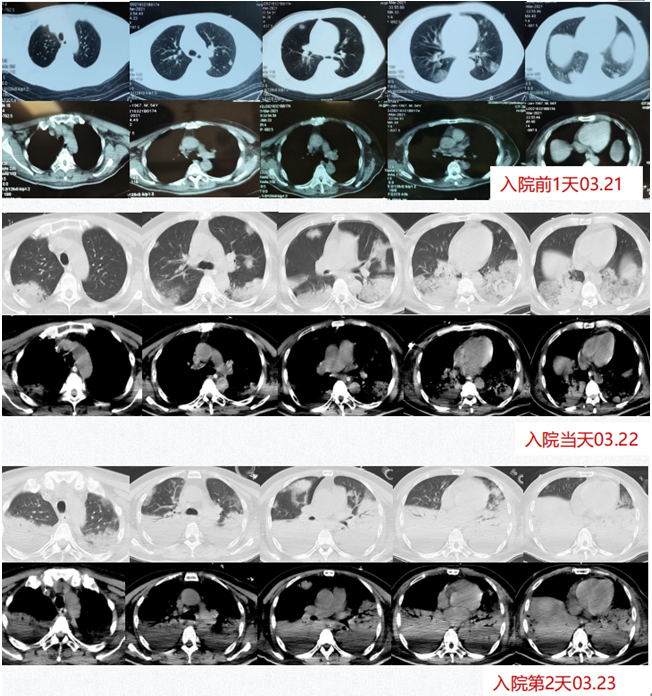

Case 3

患者,男性,54岁,意识障碍1天,高热呼吸困难2小时,2021年3月22日入RICU。多脏器功能受损,入院考虑SCAP,ARDS,脓毒血症,脓毒性休克。MODS。入科后给予脏器支持,BALF mNGS回报肺炎克雷伯菌(序列数19000),肝脓肿穿刺液培养肺炎克雷伯菌,血培养、BALF培养、脑脊液培养均回报肺炎克雷伯菌,考虑为高毒力肺炎克雷伯菌感染入血,并引起多器官感染。给予美罗培南针2.0 q8h抗感染,抗炎,CPFA,IPPV+VAV-ECMO+PPV脏器保护及支持,营养治疗。患者最终成功撤离ECMO并转至普通病房。

图片